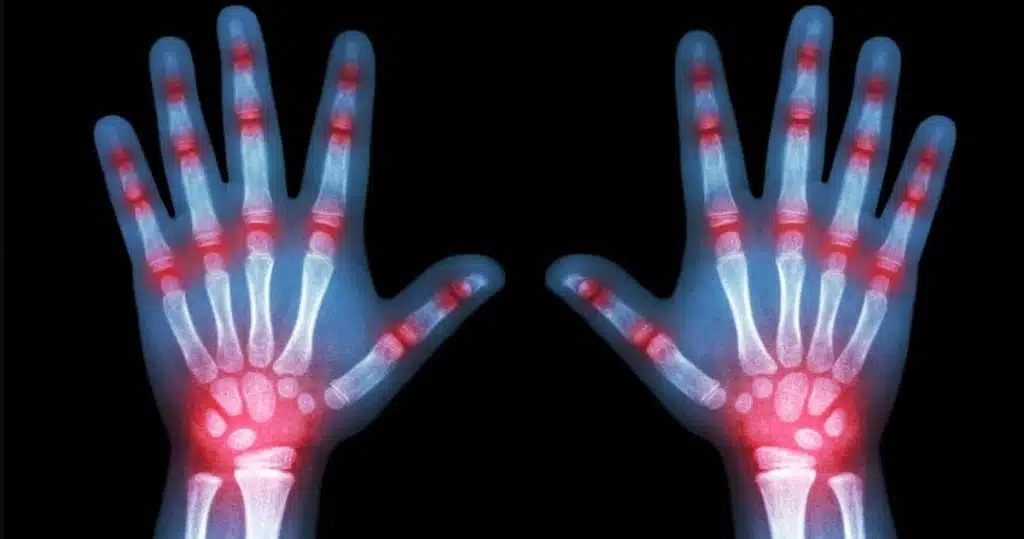

Artrita juvenilă poate apărea oricând până la vârsta de 16 ani, manifestându-se cu precădere la copiii cu vârsta cuprinsă între 2 şi 6 ani. Artrita juvenilă afectează între 80 şi 90 de copii din 100.000. Este o boală cronică ce provoacă dureri articulare și inflamații la nivelul mâinilor, genunchilor, gleznelor, coatelor și încheieturilor mâinilor, deși poate afecta și alte părți ale corpului.

Nu există un tratament pentru artrita idiopatică juvenilă. Durerea poate fi gestionată prin intermediul unor tratamente care să amelioreze simptomele, să reducă durerea și umflarea și să prevină deteriorarea articulațiilor. Medicamentele, cum ar fi metotrexatul imunosupresor și medicamentul biologic etanercept, sunt utilizate pe scară largă. Dar aceste tratamente pot avea efecte secundare, cum ar fi scăderea capacității de a lupta împotriva infecțiilor.